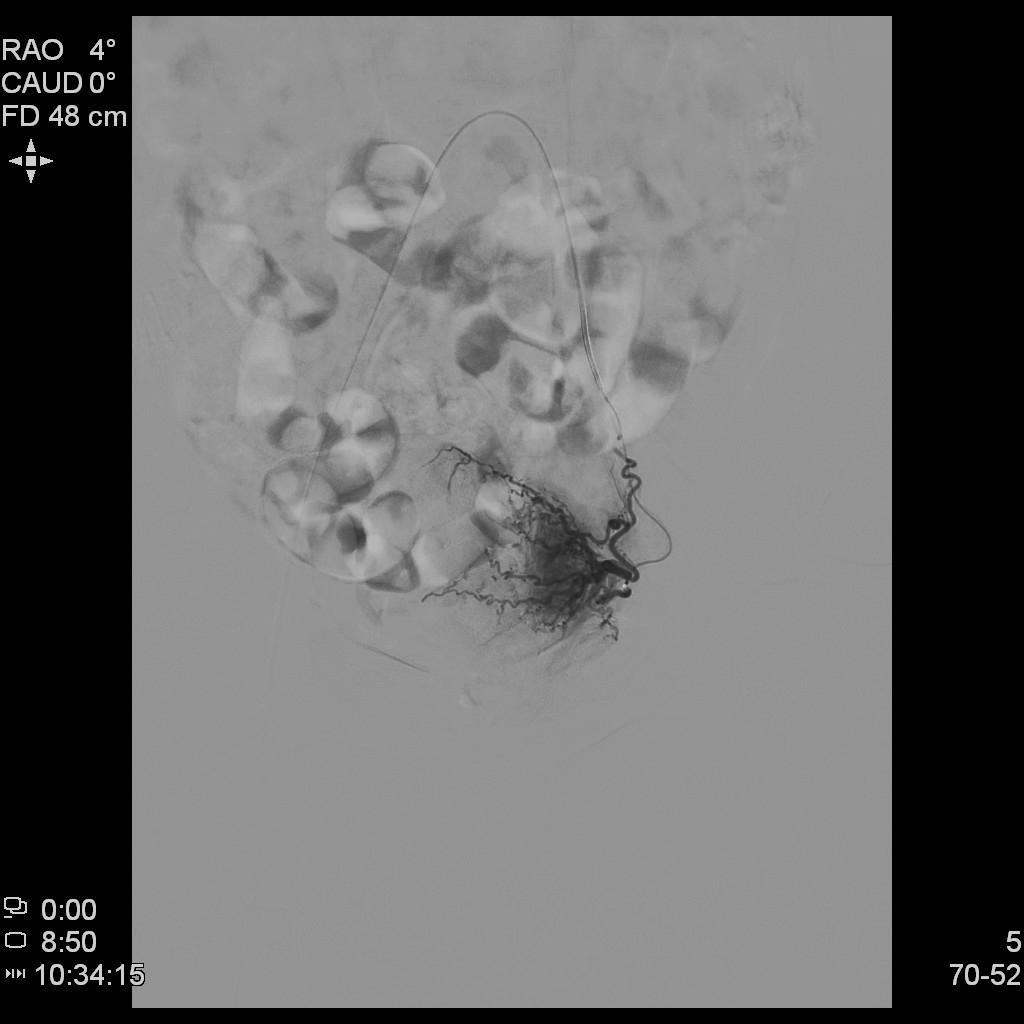

- 插管至左侧子宫动脉,显示子宫左侧病灶情况

- 插管至右侧子宫动脉,显示子宫右侧病灶情况

右侧子宫动脉造影

左侧子宫动脉造影